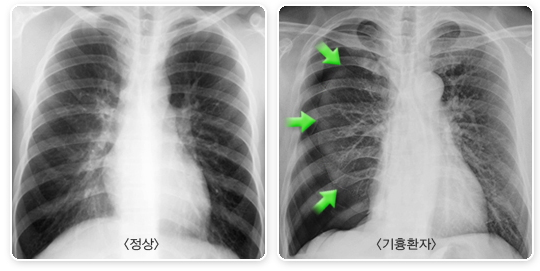

흉부 방사선 검사는 기흉의 진단과 정도를 확인할 수 있는 필수적인 검사입니다. 아래 사진에서 보이는 바와 같이 정상인의 폐는 흉강 내부 전체를 채우고 있는데, 기흉 환자의 경우 흉강 내에 공기가 차 있는 부분과 찌그러진 폐가 구분되어 보입니다.